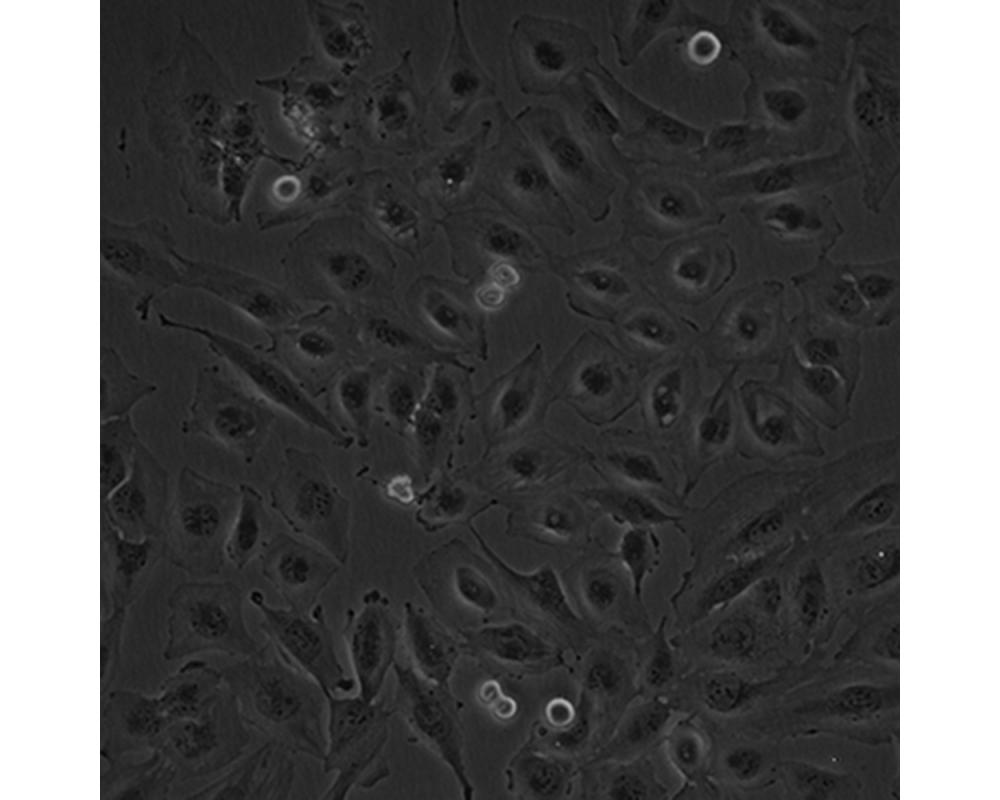

中文名稱 人腦髓母細胞瘤細胞

組織來源 成神經管細胞瘤;男性

形態特征 多邊形

生長特性 貼壁生長

特征特性 該細胞是1985年由Jacobsen PF建立的,源自一名4歲大的兒童的后顱窩腫瘤的活檢組織,未檢出神經元和膠質分化的特征;可用作轉染宿主。

培養條件 DMEM+10%FBS

傳代方法 1:4~1:6傳代;每周換液2~3次。